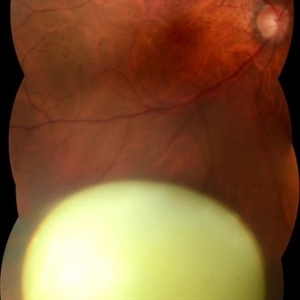

Hamartoma of the Retina

A 4-year-old male patient attended the clinic for evaluation. In the mapping examination and retina and retinography, important alterations were observed in the posterior pole of the left eye. This in turn was sent to perform the ocular ultrasonography examination, which together with the previous examinations, confirmed changes that suggested diagnosis of: COMBINED HAMARTOMA OF RETINA AND PIGMENTARY EPITHELIUM.

Photographer: JEFFERSON R SOUSA - Study Center and Ophthalmological Research Dr. Andre M V Gomes, Institute Dr. Suel Abujamra São Paulo-Brazil

Imaging device: Topcon TRC-50 DX, Imaginet 5.0, angle de 35º . Flash 36 / Mosaic with 9 images.

Condition/keywords: combined hamartoma, retinal pigment epithelium (RPE) hamartoma, tumor